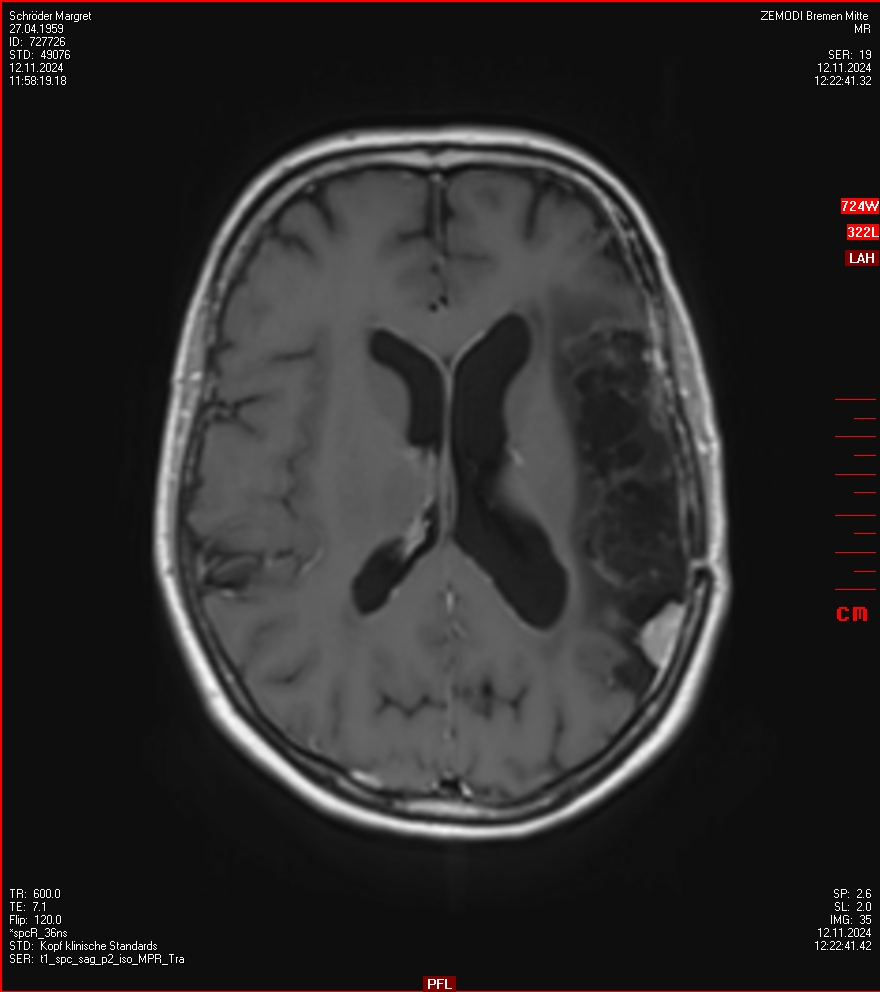

MRT vom 12. November 2024

So nun ein paar neue Bilder aus meinem Kopf. (Durch klicken bekommt man eine größe Ansicht eines Einzelbildes).

Die letzten drei Bilder Zeigen aus meiner Sicht den Tumor, der im Jahr 2021 bestrahlt wurde.

Ich denke, in den letzen 12 Monaten sind da ein paar Rezidive gewachsen,  vor 12 Monaten waren sie auch schon zu erkennen - vorher noch nicht. Nun hoffe ich auf den Rat des Spezialisten. Hoffendlich kann man etwas machen.